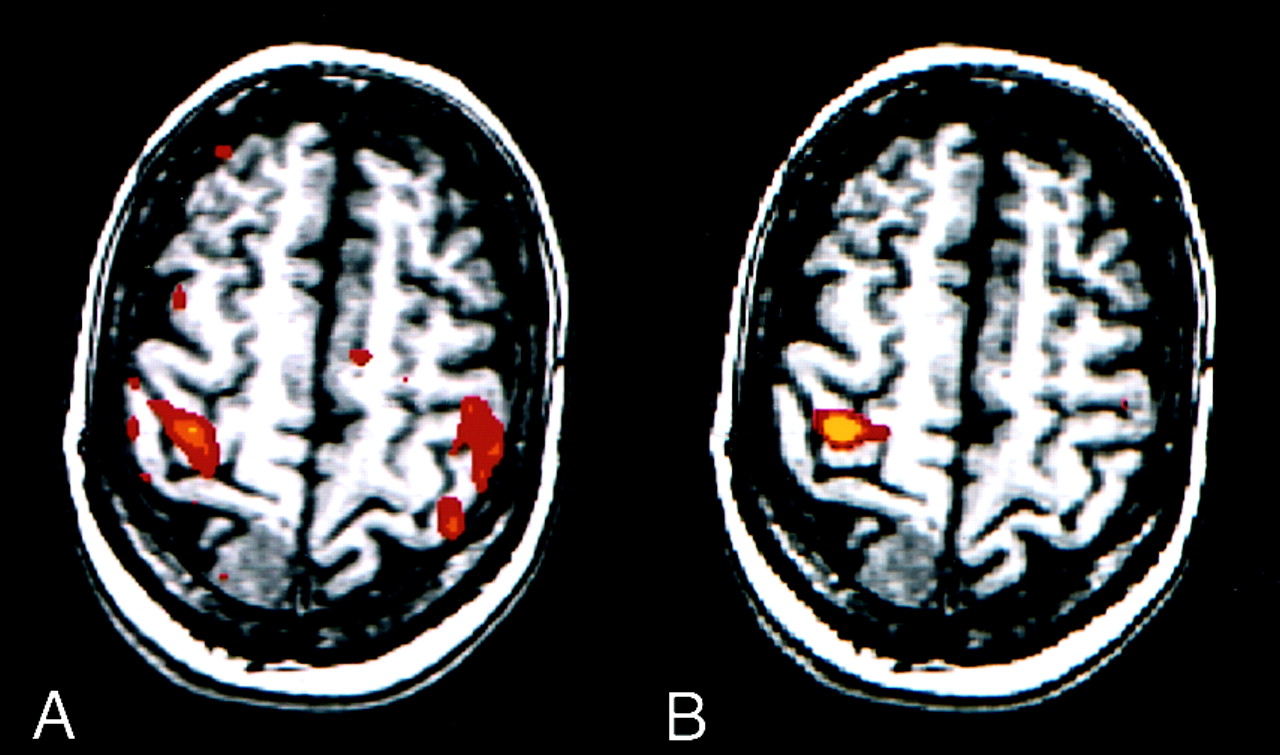

Finger-tapping task in a patient with a left temporal glioma.

A–C, fMR images. The image processed with reference function analysis (A) shows activation in the sensorimotor cortices and sensorimotor area. The image processed with ICA (B) shows a similar pattern of activation. The intersect map of pixels identified on both the image processed conventionally and that processed with ICA (C) has a high CR (83%). Note the similarity of the three maps.

D, Time course plot of the activated voxel shows that the changes in signal are temporally correlated with task performance.

E, Temporal pattern of a selected ICA component (representing the highest z score) has a .64 correlation between the time course of the component and the boxcar reference function.